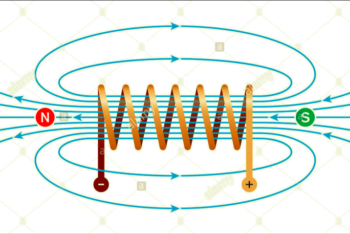

IL CAMPO MAGNETICO AD ALTA INTENSITA’

Nello specifico un Campo Magnetico ha delle potenzialità enormi che spesso non vengono prese in considerazione poiché sono necessarie, per avere effetti interessanti, esposizioni per tempi molto lunghi (alcune ore) ma se si riuscisse ad avere una forza motrice elevata (intensità di campo), lavorando con le basse frequenze, puoi ottenere notevoli effetti immediati e sopratutto duraturi su:

Attraverso il controllo della focalizzazione dell’energia e delle variabili di trattamento quali:

- Variazioni di frequenza

- Variazioni di ampiezza dell’intensità

- Andamenti di campo (rettangolare, Trapezoidale, a Gradino)

- Fronti di salita e di discesa

è possibile selettiva un lavoro di tipo bioelettrico o vibratorio